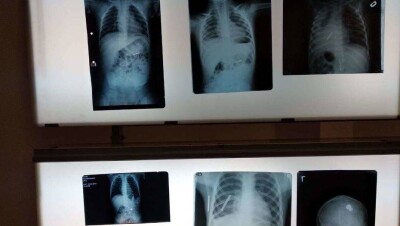

В Астане врачи спасли жизни 130 детей, проглотивших различные предметы